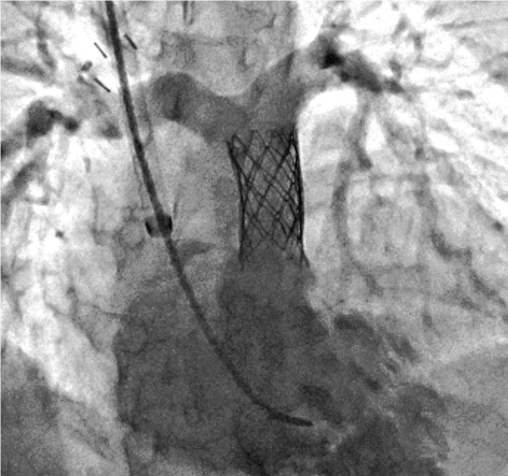

Stent Enhancer* забезпечує візуалізацію стента за рахунок придушення анатомічних структур та фонового шуму.

Stent Mode забезпечує покращену візуалізацію стента в реальному часі без необхідності додаткової окремої обробки або післяобробки.

Встановлення стенту

Встановлення клапану Melody®

Контрольна ангіографія